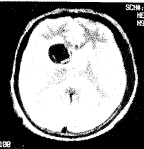

影像學檢查顱內占位性病變,如病變較小,又位於非重要功能區,臨床上可無症狀。若病變位於重要的腦功能區或病變範圍較大,臨床常出現顱壓增高的症狀(如頭痛、噁心、嘔吐等)和局灶性的神經體徵。較大的占位性病變,造成顱壓過高,壓迫腦組織,可造成肢體癱瘓,乃至形成腦疝。腦疝是危及患者生命的徵象,也是顱內占位性病變最嚴重的後果。

顱內占位性病變,常可通過影象學檢查獲得確診。影象學檢查包括頭顱CT掃描、核磁共振檢查及腦血管造影等。現代影象學檢查可顯示占位性病變的位置、大小、形態、數目,還能觀察到病變內部是否有囊變、壞死、鈣化、出血等。腦血管造影是根據血管的部位、形態的改變、循環時間的改變以及病理血管的出現等,間接了解病變的位置、大致形態、含血管是否豐富等。